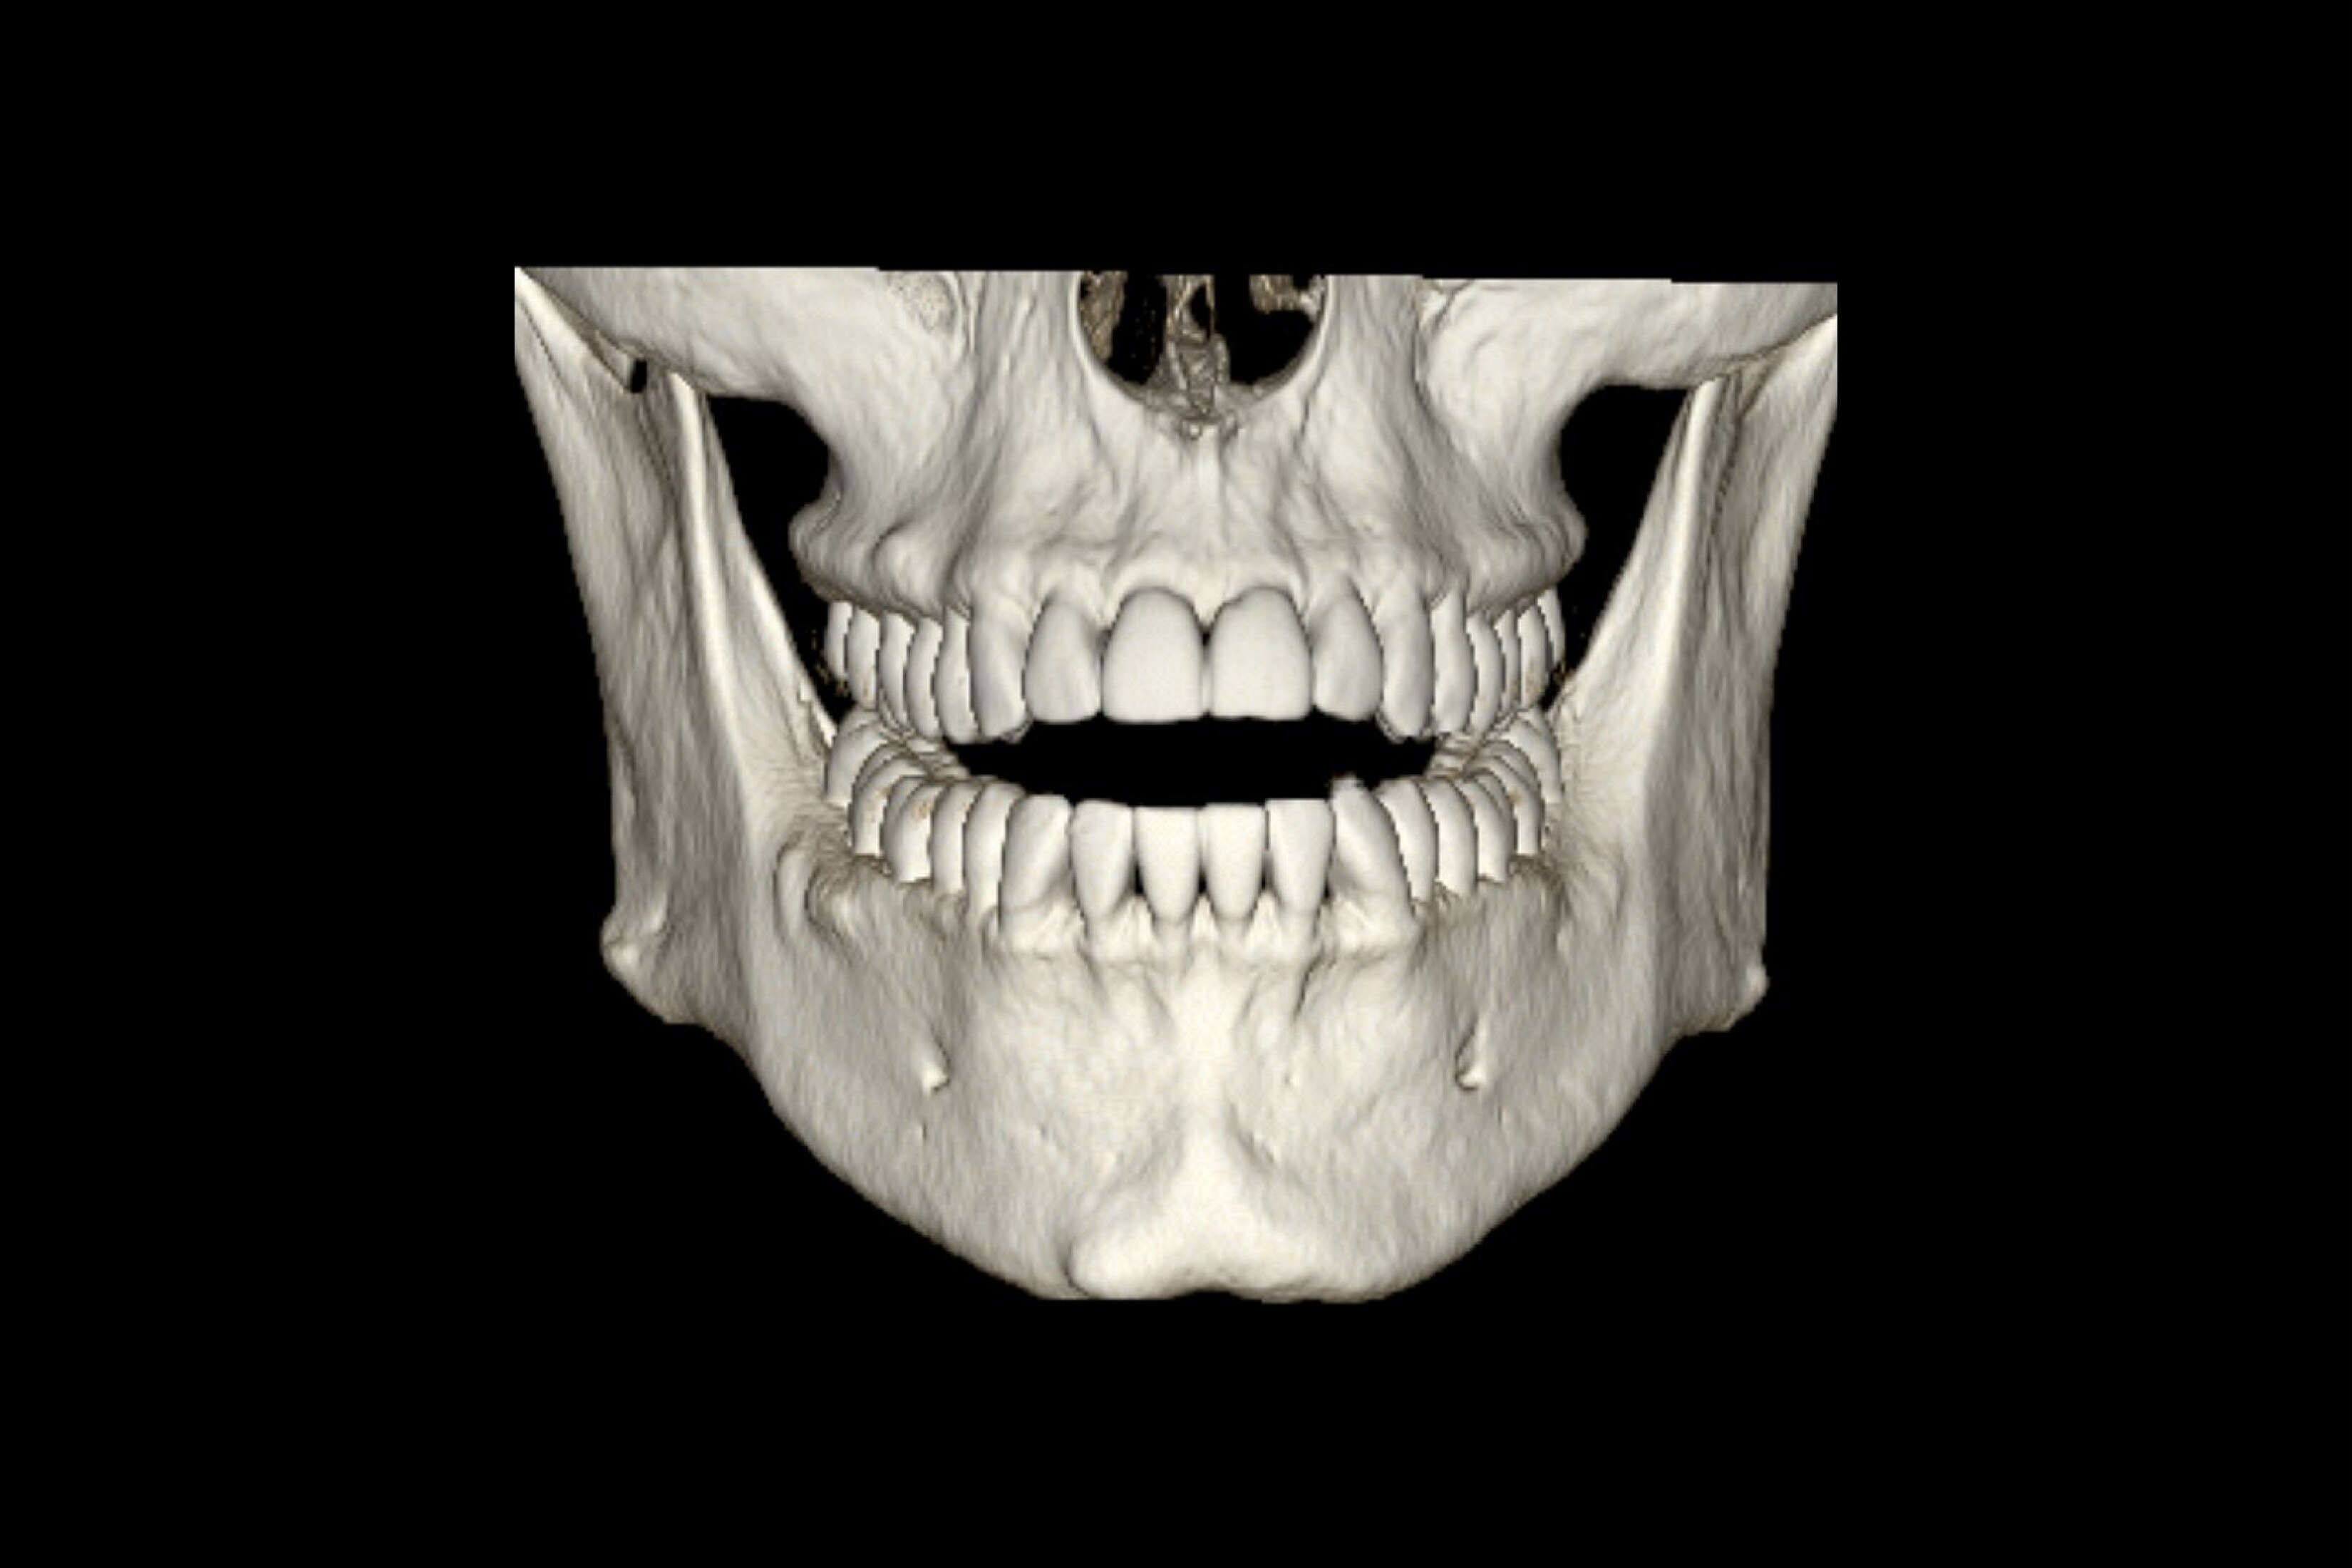

Üstün görüntü kalitesi

Daha net görüntüler daha kolay tanılar anlamına gelir ve derin öğrenme teknolojimiz AIR™ Recon DL ile olağanüstü kalitede görüntüleri daha hızlı elde edebilirsiniz. Çok çeşitli anatomiler için en net sonuçları sağlayarak MR görüntülerini görüntüleme biçiminizde devrim yaratır.

Ayrıca, göz yorgunluğunu azaltabilen okunması kolay, yüksek kaliteli taramalarla elde ettiğiniz görüntülerin kalitesinden daha emin olarak oluşturulan raporların daha iyi bir genel deneyime sahip olmasını sağlayabilirsiniz.